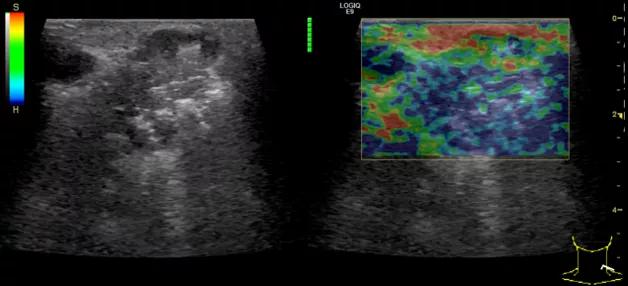

第二例是食管癌患者,术后半年余锁骨上固定淋巴结可触及肿大,疼痛非常明显,系统治疗后无缓解,患者希望通过局部处理缓解症状。造影显示强化信号明显,结节部分区域坏死,故主要针对强化区域从后向前的逐层的消融,皮下进行液体隔离减少烫伤。热消融后影像显示血流增强消失,弹性、硬度增高,一个月后复查显示充盈缺损,完全消融,疗效远超预期。

(病例2图例)